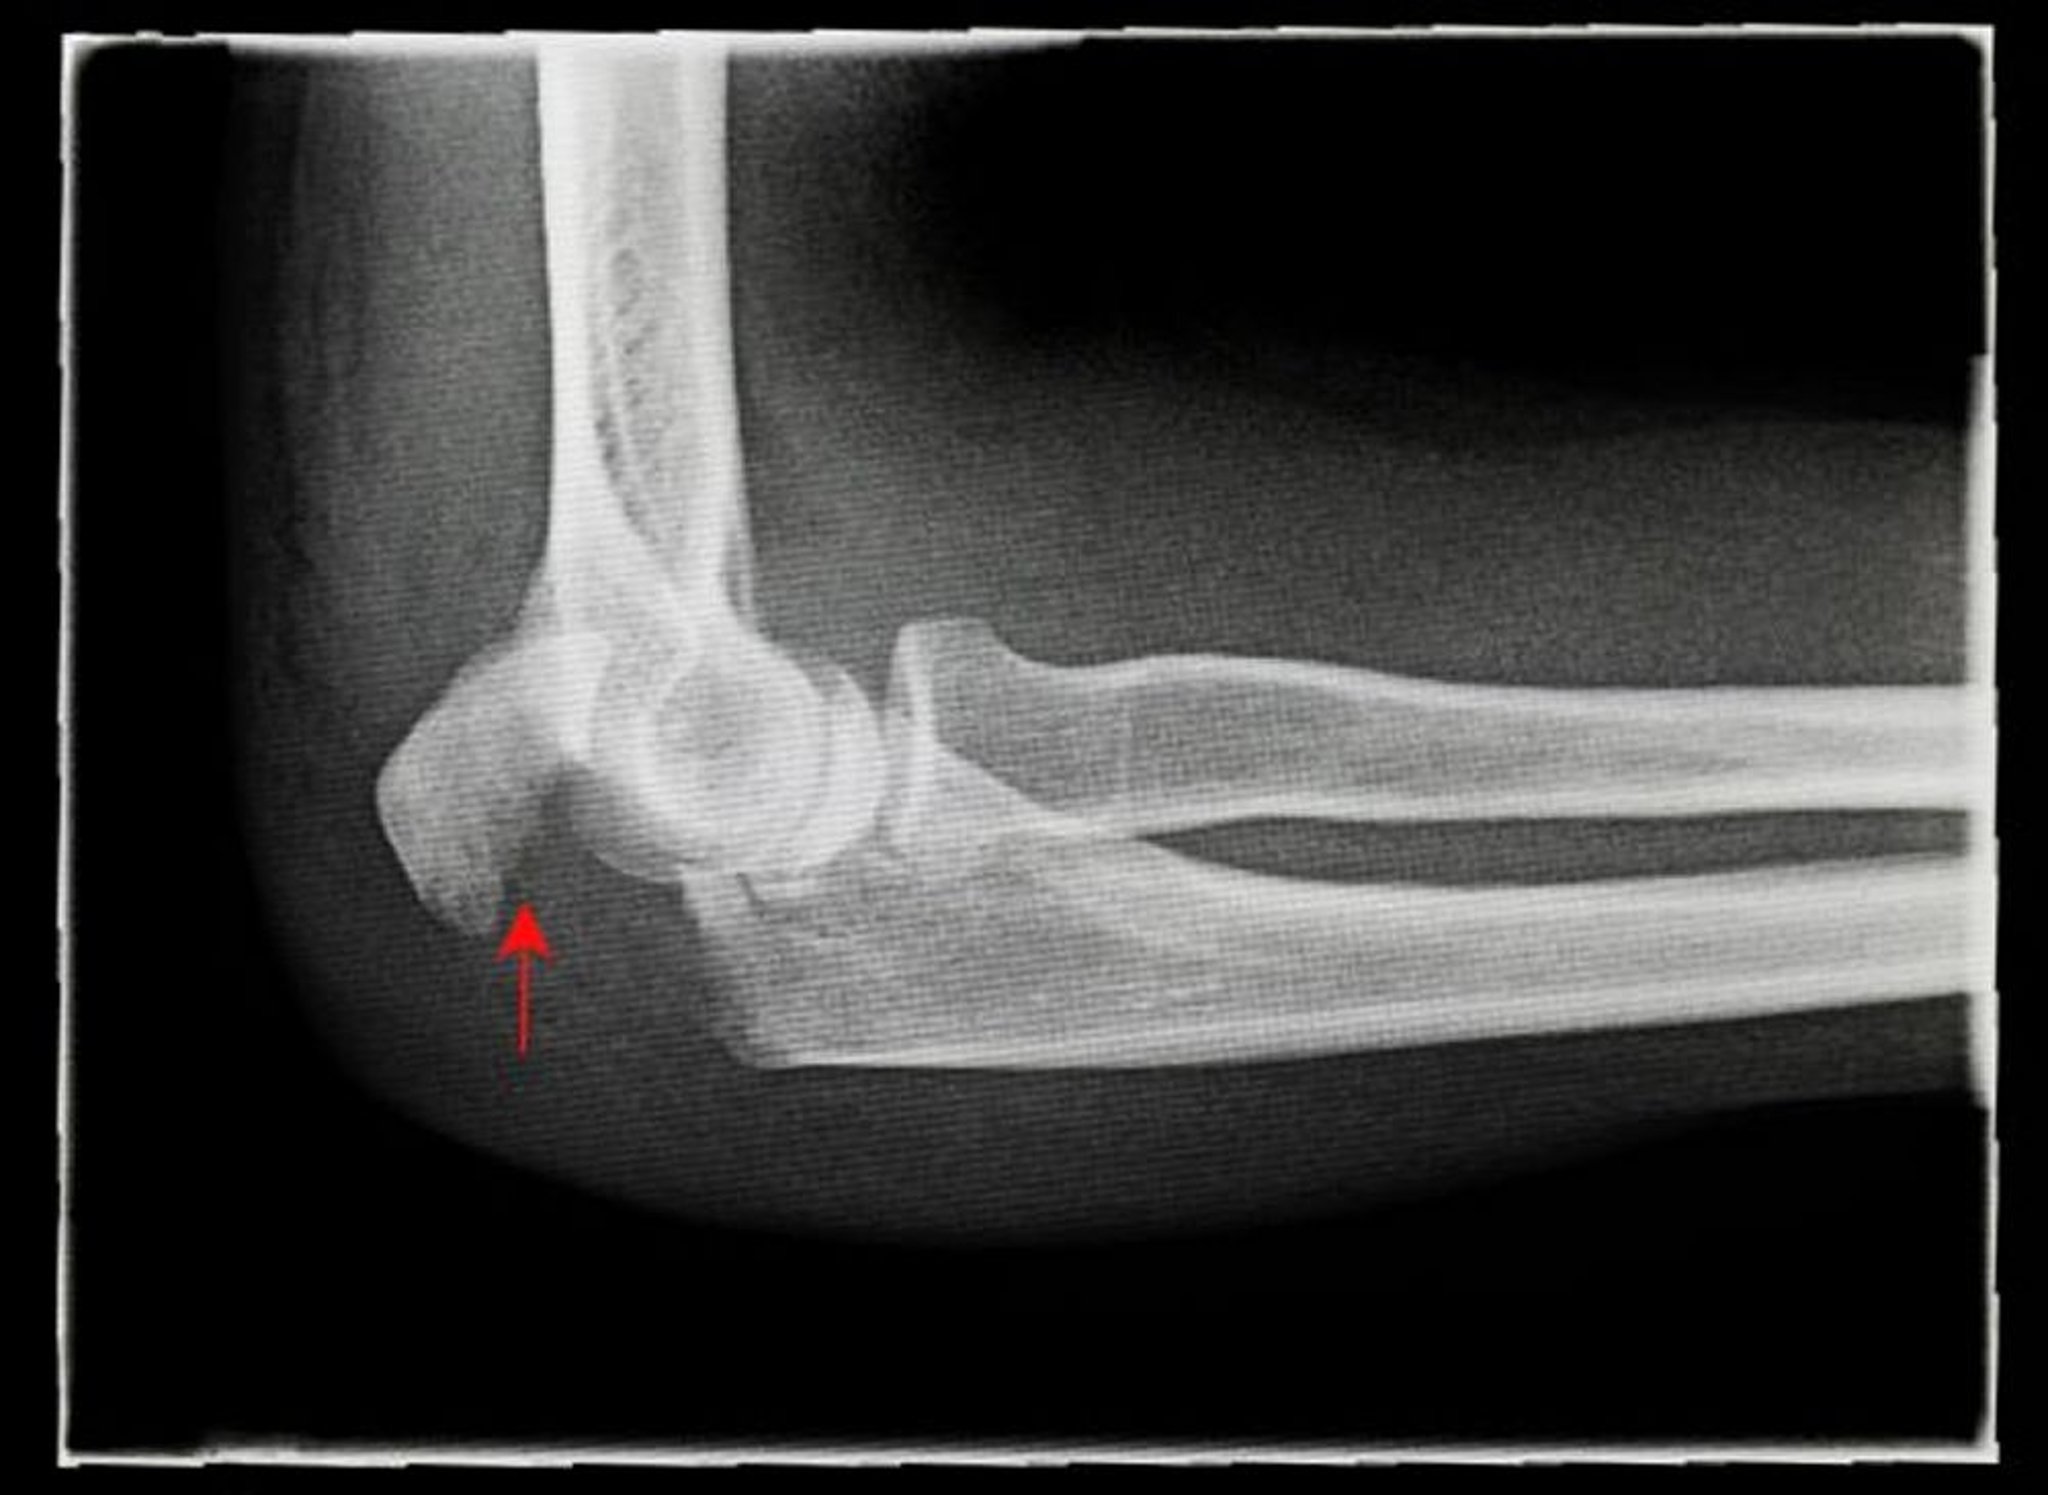

Fractura del olécranon

Esta radiografía lateral muestra una fractura de olécranon desplazada (flecha).